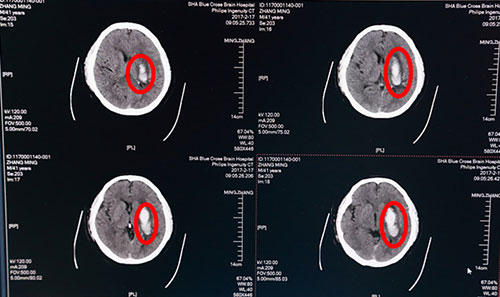

2月17日,张先生来蓝十字脑科就诊,并慕名找到李振并主任。此时距患者发病已6天,急查头颅CT示:1.左侧基底节区脑出血(急性期),部分蛛网膜下腔渗出;2.脑干、双侧基底节区腔隙灶,初步诊断为:高血压脑出血,运动性失语,肺部感染,高血压病III级(很高危),高血压性心脏病,II级糖尿病。考虑到患者病情不容耽搁,保守治疗效果不佳,两次出血35ML,有再出血可能,手术指征明确,征求家属意见后,遂决定紧急为张先生实施“颅内血肿微创清除术”进行治疗。

术前头颅CT:红圈内白色部分为脑出血血肿